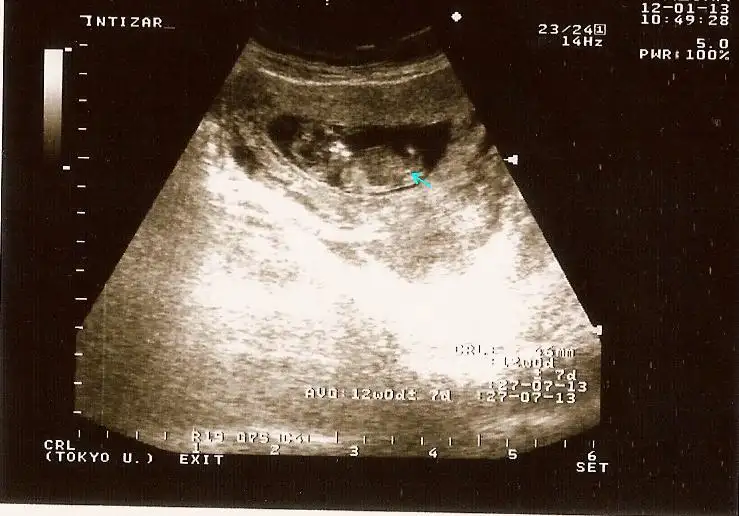

orkdm bide bu resimler var 12.13 haftalik burda kusura bakma zanada zahmet oluyo hakkini helal et orkdm.

merhaba benım ultrason sonucuda burada bakabılırmısınız acaba ...13+ lardaykenkı ultrason...